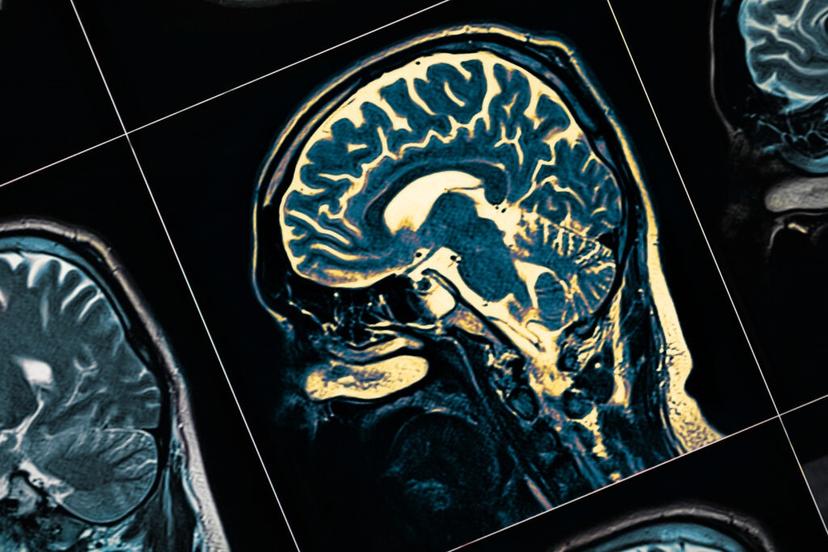

PharmaKure, a clinical stage pharmaceutical company developing precision medicines for Alzheimer’s disease (AD) and other neurodegenerative diseases, has announced a new epigenetics collaboration with Sheffield Hallam University, UK. This partnership will focus on ‘gene-based environmental biomarkers’, known as epigenetic markers, for calculating risk scores for AD. Together with ALZmetrix™, PharmaKure’s blood-based biomarker, this will increase the power of current Alzheimer’s diagnostics.

The collaborative study between Sheffield Hallam University and Pharmakure aims to gain a better understanding of AD in order to identify those more at risk of developing the disease, so enabling the provision of appropriate interventions much earlier in the disease pathology.

AD is a multifactorial disease, and it is known that environmental factors can make an important contribution to triggering it. The study’s main hypothesis is that there is differential methylation in certain target genes related to AD compared to non-AD controls. If this hypothesis proves to be true, Pharmakure can start the validation of an epigenetic predictive risk score for cognitive impairment and AD.